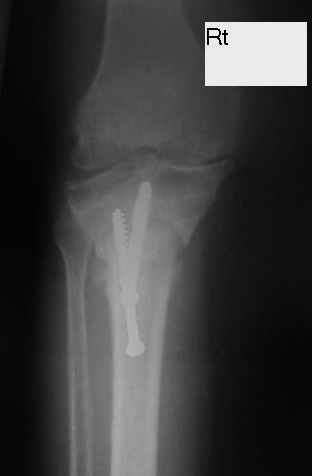

Dorogie Kollegy,Ko mne obratilas' bol'najia, ei 64 goda, ona stradaet ot dvuhstoronnego varusnogo gonoartroza, ei bila vipolnena Visokajia Ostotomjia goleny sprava 01.06.2004, zona osteotomii ne sroslas', plastina bila udalena 12.09.2004 (vidimo iz-za ee nestabilnosti), zona osteotomii tibia bila fixirovana 3-mjia shurupami. Seachas sylno bespokoyat boly v dvuh sustavah, hodit s trudom s pomoshyu Walker, a voobshe ona seachas na invalidnoi kolyaske. Podzkazite, pozhalusta, kak mozno ei pomoch' (snimky prilagayutsa)

U bol'nogo non-union osteotomii tibii. V vozraste 64 let, sdelal bi sleduiezhee:

Work out, proverit', net li infection: ESR, CRP, White cell Scan. Esli infection net togda est' dva varianta:

1. I predpochel bi ego: Total Knee Arthroplasty. Nuzhen budet Revision ( Long stem) tibial Component.

2. Ne sovetuiu delat' geroicheskix postumkov v otnoshenii Non union. Tut est' mnogo problem, ved' esteotomia provedena ne pravili'no s tochki zrenia deformazii. Orientazia ploskosto kollennogo sustava xotia ne ploxa v sagital'noii ploskosti, no vo frontl'noi idet sil;noie otklonenie narozhu i vniz. A nam tida ne nado.